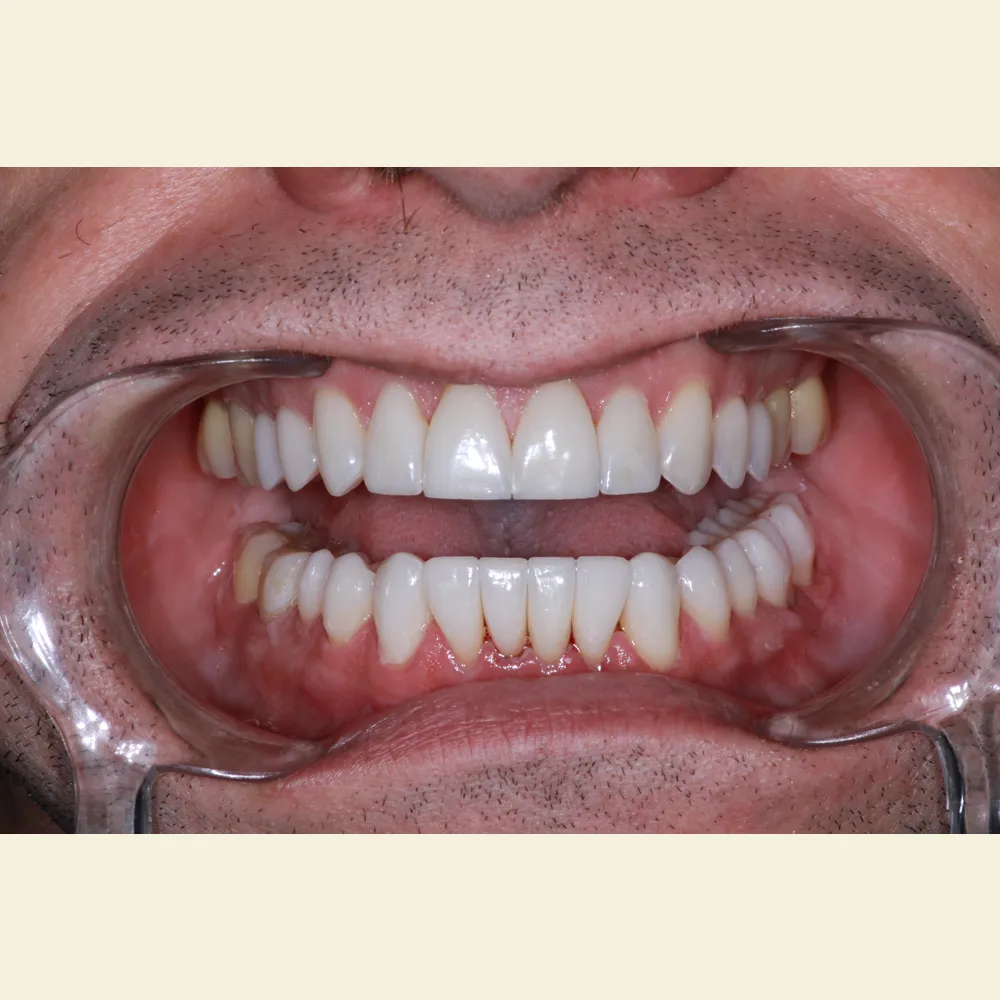

Real Stories, Real Results: Case Studies Showcasing How Our Personalized Approach Transforms Smiles and Lives

Complex Cases

Witness the Remarkable Changes We Can Achieve

Ultra-thin veneers are crafted from high-quality materials that closely resemble the look and feel of natural teeth. The translucency and texture of these veneers mimic the appearance of real enamel, ensuring that your smile looks natural and aesthetically pleasing. Each veneer is custom-made to match the color, shape, and size of your existing teeth, blending seamlessly with your natural smile. This attention to detail ensures that your veneers are virtually indistinguishable from your natural teeth, providing you with a flawless, beautiful smile.